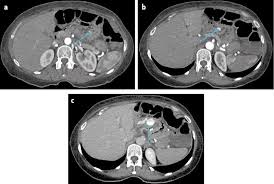

Tricky Internal Hernias Ten Signs To Improve Your Performance European Radiology